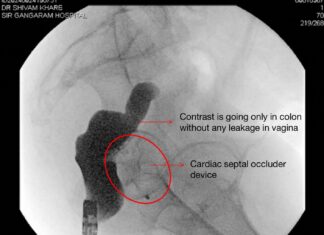

Innovative Endoscopic Surgery Rescues Abnormal Connection Between Intestine and Womb at Sir Ganga Ram...

New Delhi – In a remarkable medical breakthrough, doctors at Sir Ganga Ram Hospital, New Delhi, have successfully treated two women suffering from complex fistulas—abnormal communication between the large intestine and womb—using an innovative...